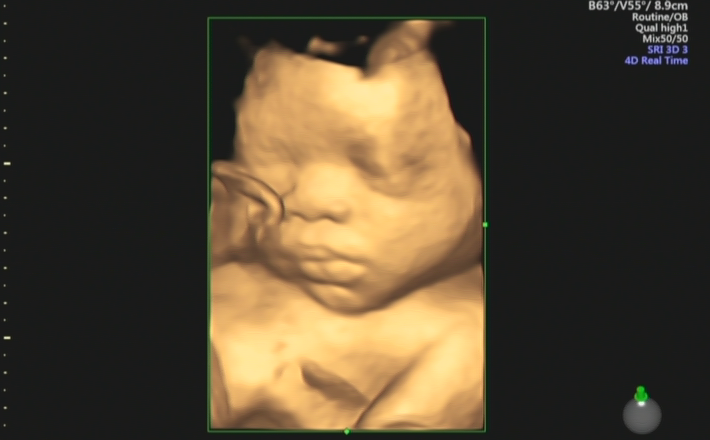

孕中期四维大排畸

B超大排畸是孕中期的关键产检,可以通过四维彩超、系统超声、心脏彩超等项目排除大部分胎儿发育畸形。

检查时间:单胎时间是在22-28周为佳;双胎时间在20-24周为佳。

主要筛查缺陷:主要是观察胎儿在宫内的情况,通过检查五官、四肢、骨骼、心脏、肾脏各器官的症状表现,判断胎儿是否健康,是否存在发育畸形的问题。

我院还美国GE系列超声仪器,细致的多切面成像分析胎儿的解剖结构及发育状况,能够提供更多、更精准的图像数据,可以更加清晰、完整地记录胎儿宫内的高清动态,满足从早孕期到孕晚期的全程早期检查和诊断。